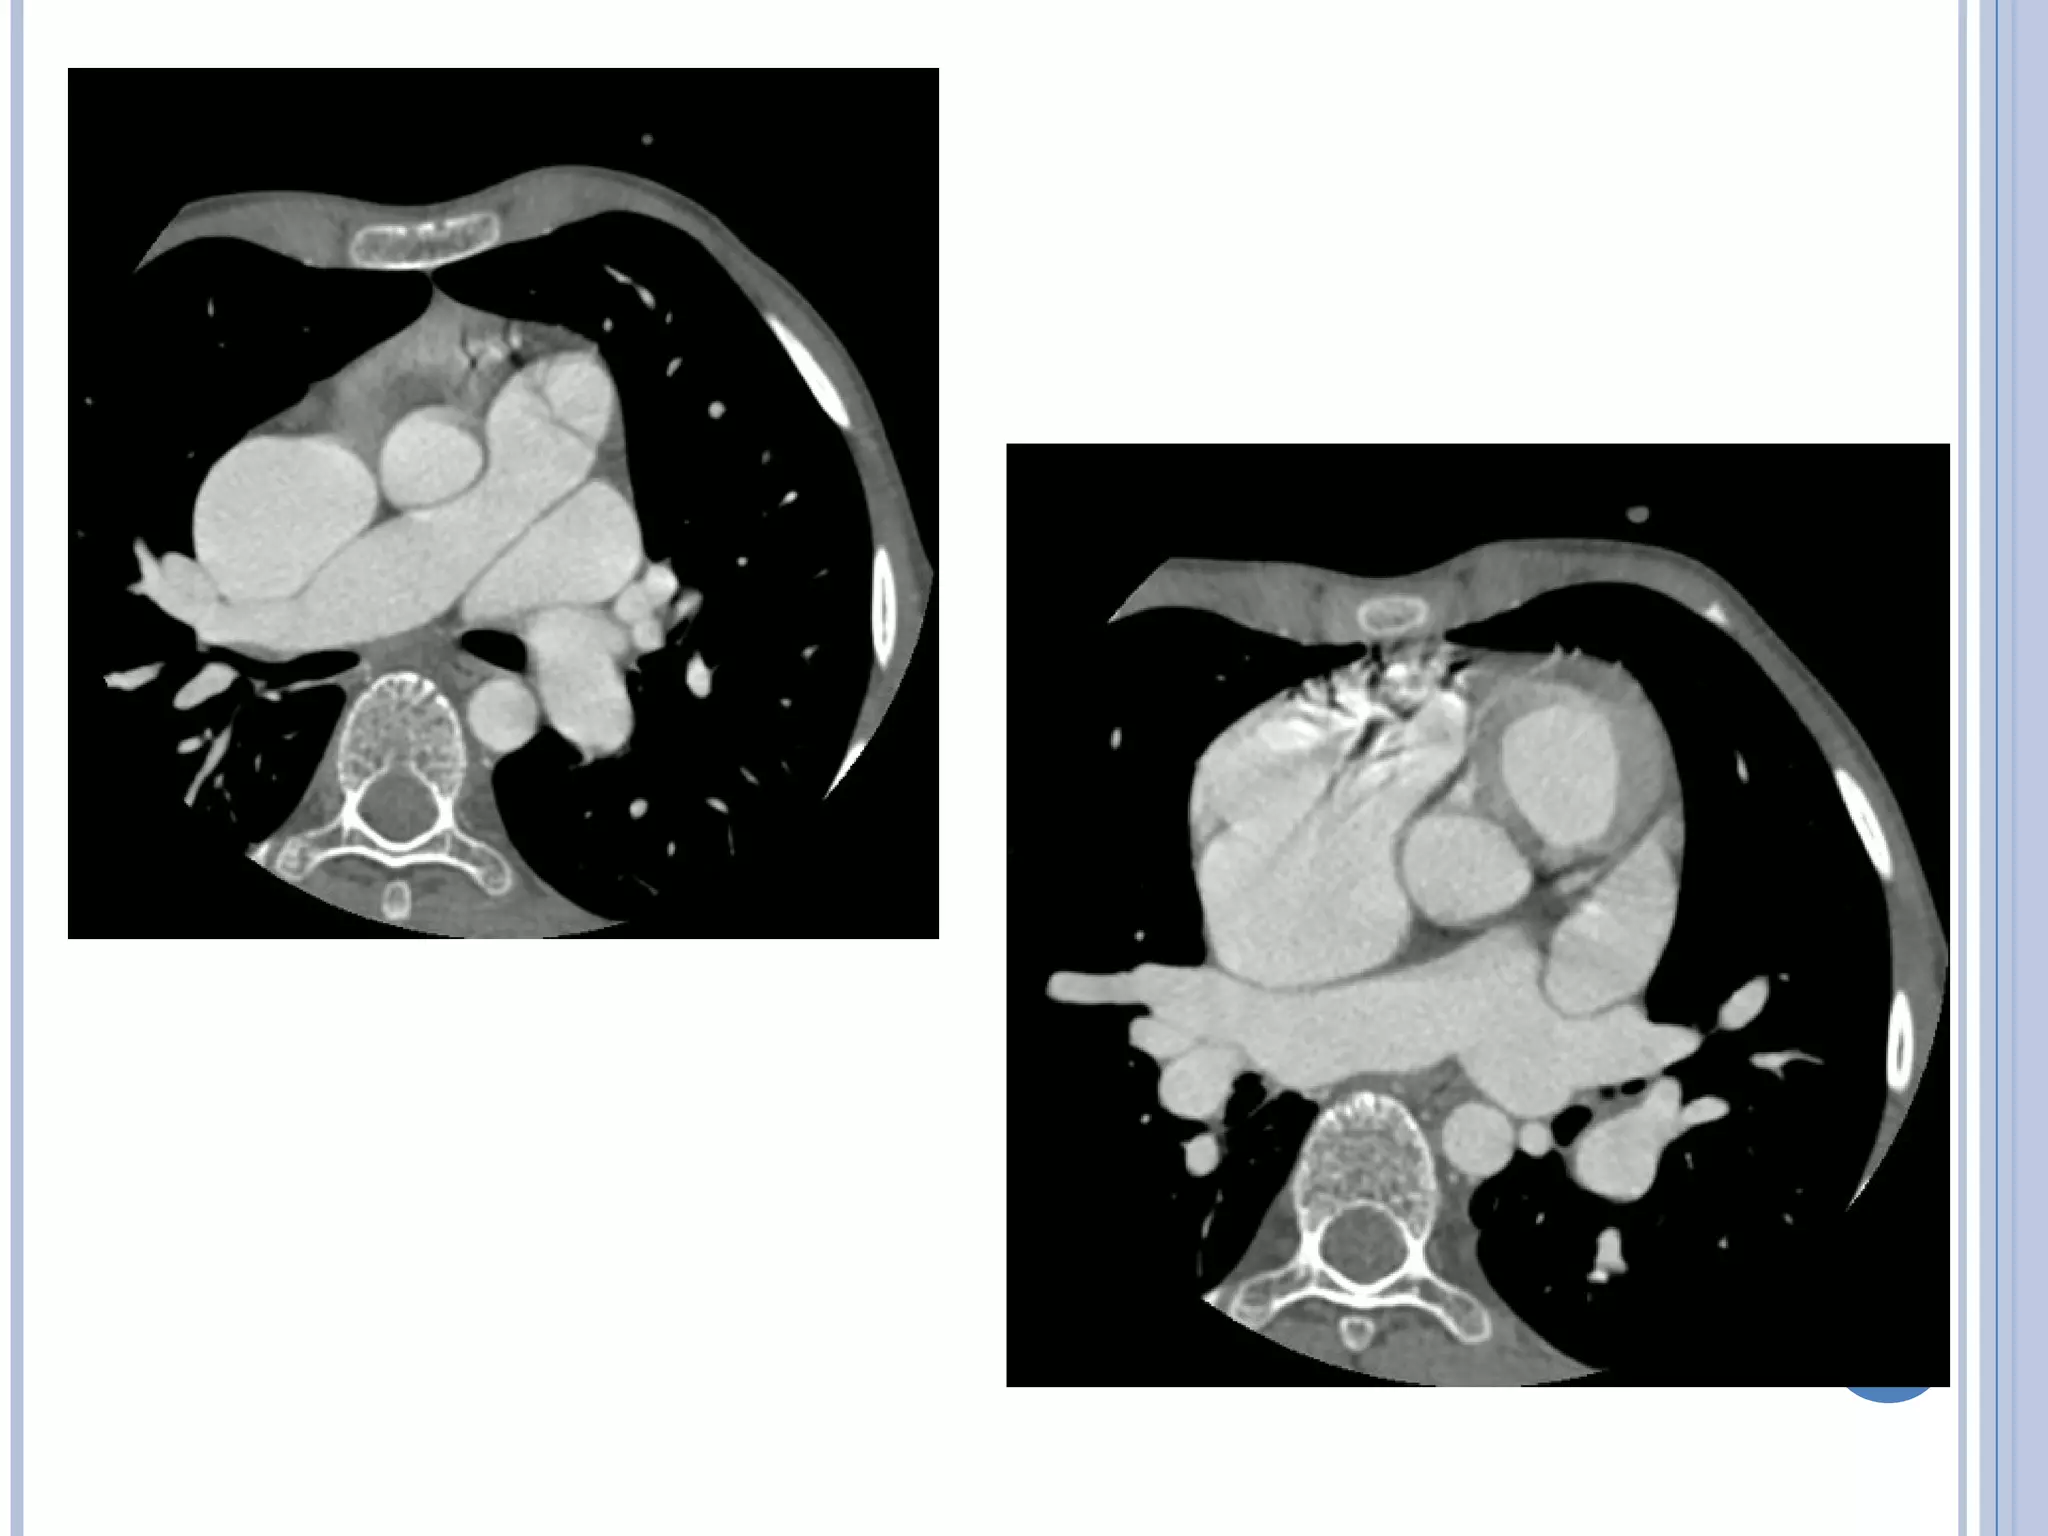

THE TREE IN WINTER –

INFRACARDIAC TYPE

THE TREE INWINTER – INFRACARDIAC TYPE